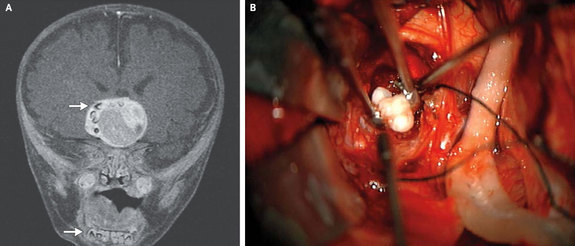

Một em bé 4 tháng tuổi ở Maryland được phát hiện có chiếc răng trong não. |

Sau đó, em bé đã trải qua phẫu thuật não để cắt bỏ khối u. Trong đó, trong đó các bác sĩ phát hiện ra rằng khối u này đã phát triển thành chiếc răng hoàn chỉnh.

Các bác sĩ đoán định có thể đây là một loại hiếm gặp của bệnh u não. Sau khi phân tích các mô khối u, em bé được xác định có u so hầu Craniopharyngioma - một khối u não thuộc loại hiếm có thể phát triển tới kích cỡ lớn hơn một quả bóng golf, nhưng rất may là loại u này không lây lan.

Tiến sĩ Narlin Beaty - một giải phẫu thần kinh tại Đại học Trung tâm Y tế Maryland cũng là người thực hiện phẫu thuật cho đứa bé cùng với đồng nghiệp của ông - tiến sĩ Edward Ahn của Trung tâm trẻ em Johns Hopkins cho biết trên tạp chí New England Journal of Medicine rằng rất có thể khối u được hình thành từ các tế bào hình thành răng.

Craniopharyngioma được biết thường chứa canxi nhưng chưa bao giờ nhìn thấy trên thực tế có những khối u thế này mà chứa răng cả.